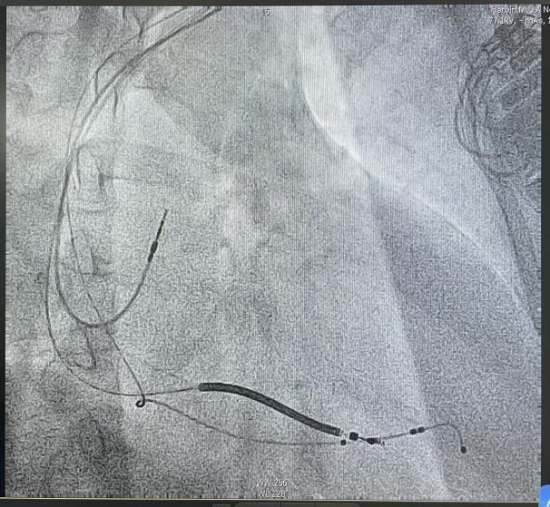

术后影像

手术由曹雪主任医师和孙丽秀副主任医师实施,团队成员默契配合,术中精准完成冠状静脉造影定位,凭借丰富的介入操作经验,顺利将左室主动电极通过侧螺旋固定模式,精准植入到最优起搏靶血管位置,完成左室电极的植入与固定。经牵拉、推动测试,电极稳定性极佳,起搏阈值、感知、阻抗等各项参数均达理想标准。术后患者心脏电同步性显著改善,无任何手术并发症,各项生命体征平稳,心衰相关症状明显改善。

术中,造影显示患者冠状静脉靶血管直径粗且走行平直,若采用传统被动固定左室电极,不仅难以精准定位起搏靶点,术后电极脱位风险也显著升高,还可能增加术后CRT无应答风险。为追求更优的手术效果、提升患者长期预后,曹雪教授团队决定为患者采用新型左室主动固定四极电极实施CRTD植入术。该新型主动电极配备了侧螺旋固定装置,可以主动旋入血管壁,不仅能突破血管形态限制,精准选择最优起搏靶点,最大化改善心脏再同步化效果,大幅提升患者术后治疗反应率,更显著降低了术中术后电极脱位的风险,为患者长期稳定的疗效提供了坚实保障。